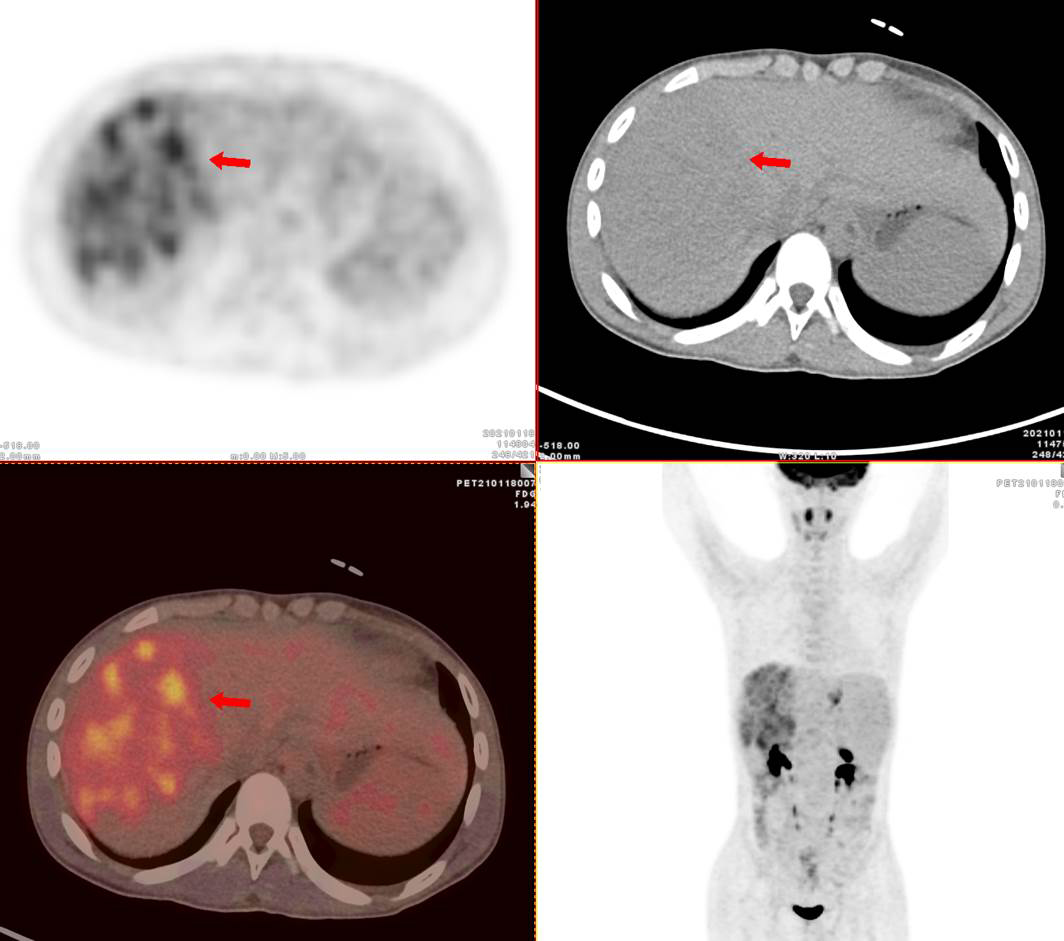

13歲男孩小新,因腹瀉就診,外院CT發(fā)現(xiàn)肝臟多發(fā)占位,考慮肝癌并肝內(nèi)轉(zhuǎn)移,肝硬化、門靜脈癌栓形成。為了查找病因及進(jìn)行更深入的檢查,小新一家選擇進(jìn)行全身的PET/CT檢查。據(jù)悉小新有乙肝病史10年。

PET/CT顯示肝臟明顯增大,肝內(nèi)見10.6x8.1cm稍低密度腫塊,F(xiàn)DG攝取不同程度最高,SUVmax 2.5-5.5。門靜脈增寬,F(xiàn)DG攝取不高,脾臟增大。

PET/CT診斷 :原發(fā)性肝細(xì)胞肝癌;門靜脈高壓